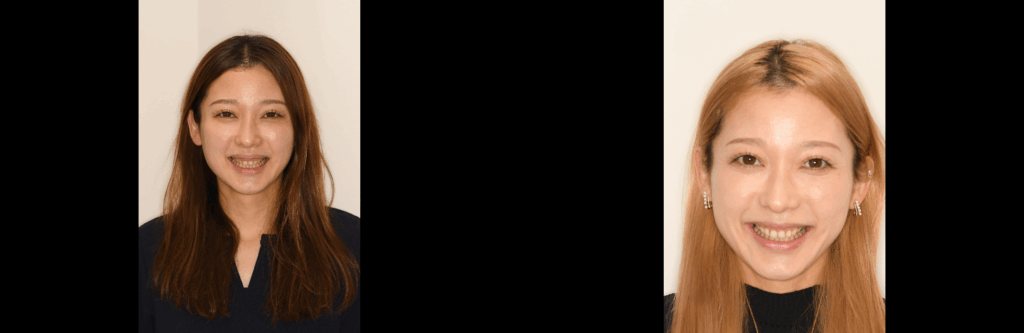

■ 術後の変化と患者さんの声

治療後

治療前後比

術後の腫れも最小限で、回復も良好。

そして何よりも、笑顔が見違えるほど自然に✨